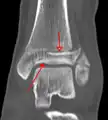

Une fracture triplane de la cheville vue sur une radiographie standard

Une fracture triplane de la cheville vue par TDM

CT

Les tomodensitogrammes peuvent être indiqués en cas de risque de fracture fragmentée ou de fracture impliquant la surface articulaire[9]. Cette imagerie peut être utilisée pour la planification chirurgicale.